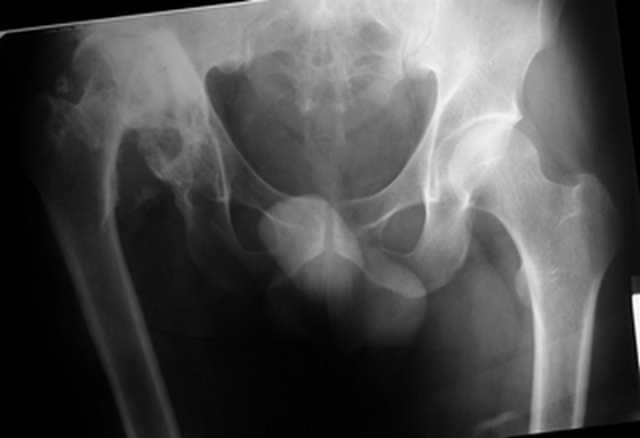

Уважаемые коллеги. Пациент 30 лет 3 года назад в результате травмы получил травматический дефект нижних конечностей до в/3 голеней, был пропущен вывих бедра.

В настоящее время очень неплохо ходит на протезах, движения в неоартрозе близки по объему к здоровой стороне. Основная жалоба - выраженная боль при ходьбе. планируем двухэтапное эндопротезирование - задним доступом мобилизовать проксимальный отдел бедра, резецировать шейку, аппаратом низвести бедро(головку оставить там где она есть, так как больших дефектов не видно(может пригодится в последующем?)). Вторым этапом бесцементное эндопротезирование. Насколько такой вариант реалистичен? Доступ для второго этапа? Может быть другие варианты?С уважением, Максим

Низводить надо обязательно, лучше в аппарате и лучше без остеотомии.

Если в аппарате низводиться не будет, то из небольшого доступа, лучше под контролем С-дуги выполнить остеотомию шейки. Без предварительного

низведения максимально возможная коррекция длины - 2,5-3 см.

Решение по ВВ придется принимать по месту.... Сумеете "подрыться" и получить хорошее покрытие чашки (+2 винта об-но) - хорошо, если нет -

костная аутопластика из головки.